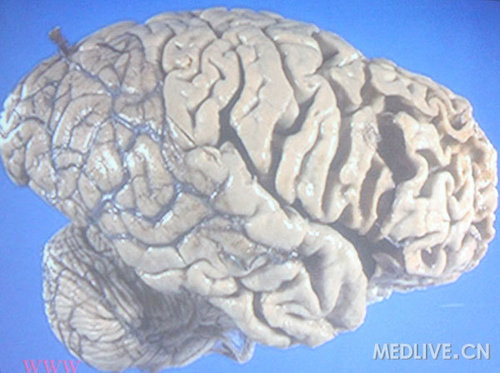

图为AD患者大脑标本可见弥漫性萎缩

脑萎缩主要累及颞叶内侧面,尤其是海马,但也可累及额叶、顶叶。